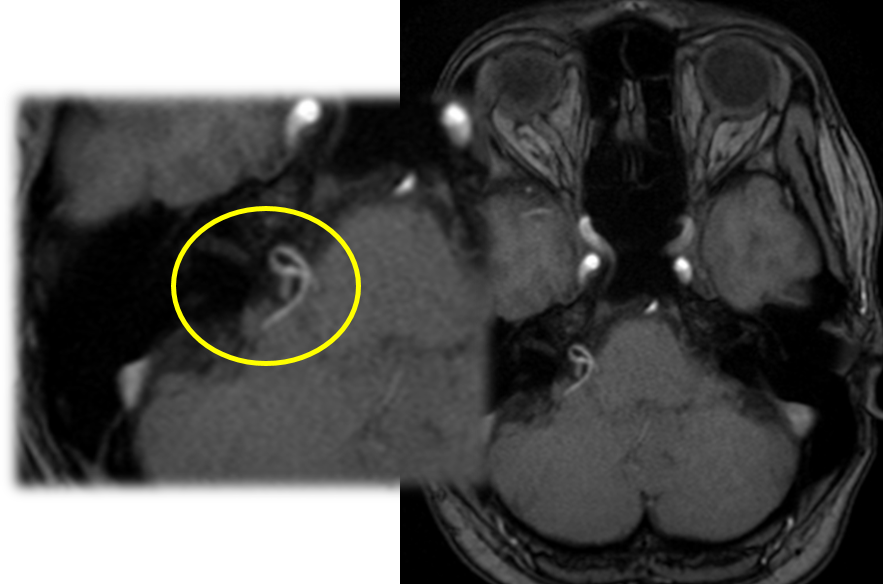

顔面神経は、脳幹から出たすぐのところで血管(前下小脳動脈など)と隣り合っています。加齢による動脈硬化などで血管が蛇行すると、この神経を圧迫しやすくなります。 血管の拍動が神経に伝わり、「異常な電気信号」が発生することで、顔がピクピクと動いてしまうのです。

顔面けいれんの確定診断と治療方針の決定には、MRI検査が極めて重要です。 当院では、3D-FIESTA(フィエスタ)やCISS(キス・シス)といった、神経と血管を非常に鮮明に映し出す特殊な撮像法を用いて、以下の情報を正確に把握します。

これらのMRI画像を3次元で再構成することで、神経と血管の位置関係を立体的な「設計図」として捉え、診断の精度を高めるだけでなく、安全な手術計画にも繋げています。

主訴:数年前からの、”右まぶた”から”頬”にかけてのピクつき

”右まぶた”から”頬”にかけてのピクつきということでMRI検査を施行すると…